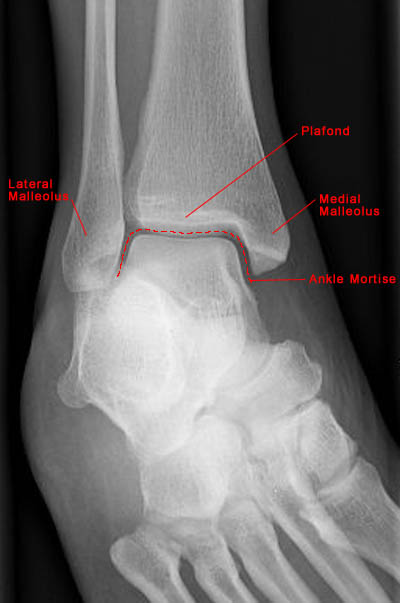

Mortise View of Normal Ankle

• Standard radiographic examination of the ankle includes AP, lateral and mortise views of the joint.

• Mortise view requires oblique examination at 20 to 30 degrees internal rotation and results in alignment of medial and lateral malleoli in the same plane.